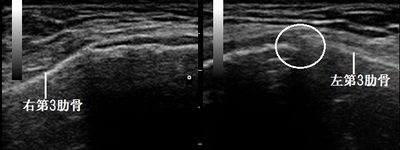

川越市若葉 主婦 交通事故 胸の痛み 肋骨損傷

左右第3肋骨 超音波長軸像

川越市若葉 60代主婦。 交通事故 胸の痛み 肋骨損傷。

【原因】

自家用車を運転中、よそ見をして前の車に衝突してしまいました。衝撃で左胸をハンドルに強打して

しまいました。

病院でレントゲン検査を行いましたが異常は見つかりませんでした。バストバンドで固定し、自宅で

安静にしていましたが深呼吸や腕を高く上げようとしたときの痛みがなかなか軽減しませんでした。

2週間後、当院に来院され超音波検査を実施したところ、左第3肋骨の一部が僅かに損傷している様子が

認められました(画像の丸の中)。

【治療】

肋骨の損傷を修復し骨癒合を促進させる物理療法を行います。また、特殊仕様の治療機器を使用し、

側胸部や左肩周囲の筋緊張を和らげ呼吸や腕の挙上時の痛みを緩和していきます。